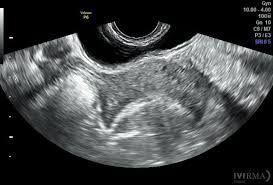

Interacción de los Ultrasonidos con los Tejidos y su Aplicación en Ecografía

Los ultrasonidos interactúan con los tejidos biológicos de manera compleja, y esta interacción depende de diversas propiedades físicas, como la frecuencia de las ondas ultrasónicas, la naturaleza de los tejidos…